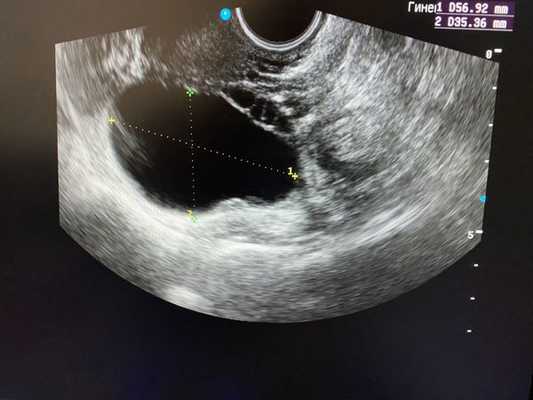

(Слева) УЗИ органов малого таза: типичная картина анэхогеной функциональной кисты с окружающей паренхимой яичника (отмечена калиперами).

(Справа) Функциональные кисты яичника могут увеличиваться, тогда окружающая паренхима яичника сжимается до тонкого ободка. Когда имеются такие проявления, как тазовая боль, необходимо использовать импульсную допплерографию для оценки форм колебаний артериального и венозного кровотоков.